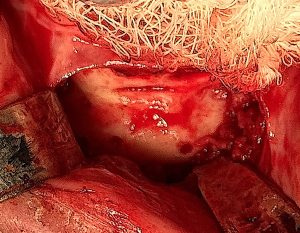

- Expect dense scar tissue and altered landmarks

- Osteotomy often must be slightly higher or lower than original cut

- Maintain ?5 mm clearance from mental foramen

- Use guarded saw + osteotomes to protect nerve